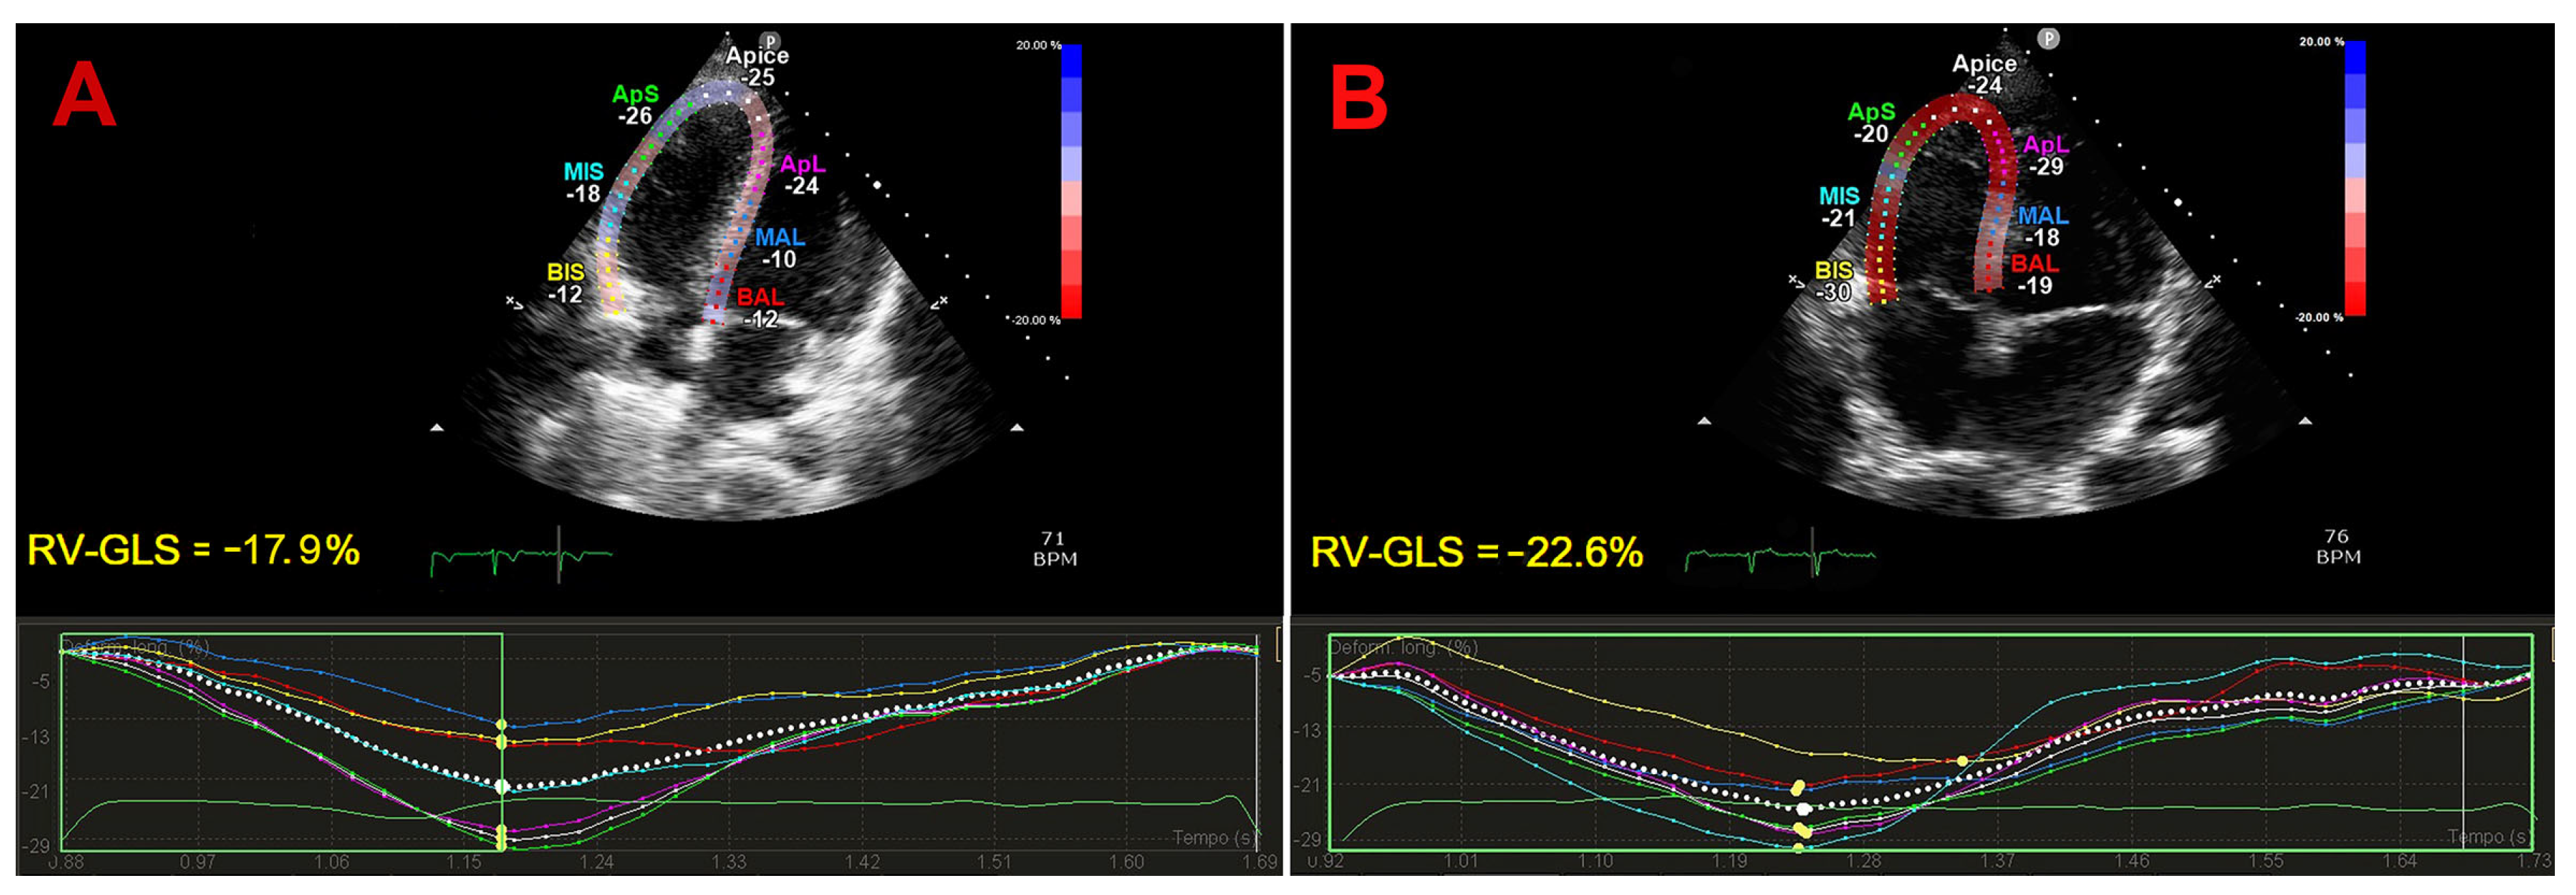

3.4. Effect of IPF on RV-GLS

| RV-GLS (%) | 18.6 (13.4–22.6) | 22 (18.4–24.2) | <0.05 | 6 (100) |